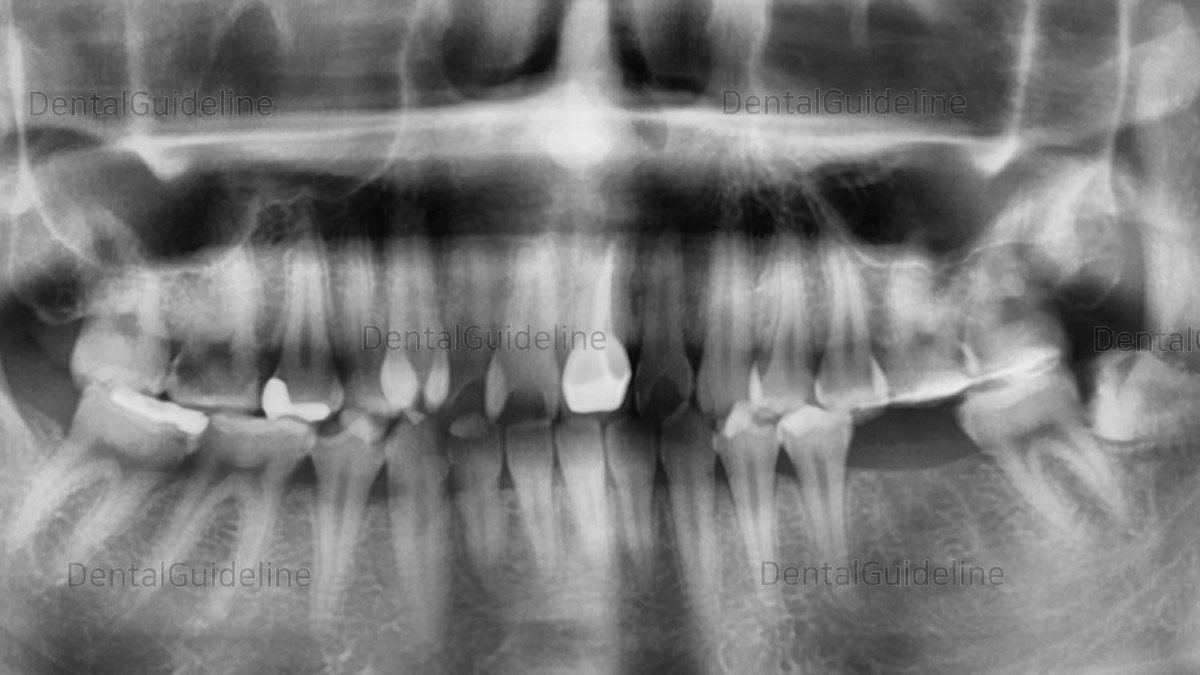

A case of a central incisor with deep caries. It was installed with PFM after root canal treatment.

Panoramic radiograph after 4 years.